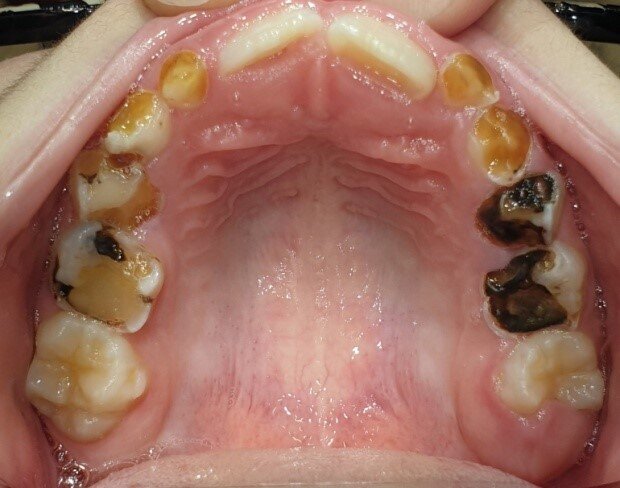

Afbeelding 4a: Kleurfoto’s op de leeftijd van 6 jaar, juli 2018. Alle cariëslaesies in de bovenkaak zijn arrested, in de 55, 64 en 65 met ondersteuning van SDF. Laesies die tijdens het aanbrengen arrested waren, zijn niet verkleurd.

Afbeelding 4b: Kleurfoto’s op de leeftijd van 6 jaar, juli 2018. Alle cariëslaesies in de bovenkaak zijn arrested, in de 55, 64 en 65 met ondersteuning van SDF. Laesies die tijdens het aanbrengen arrested waren, zijn niet verkleurd.

Jenny is 6 jaar. Er worden röntgenopnames en kleurenfoto’s gemaakt (Afb. 3 en 4). Op de röntgenfoto’s lijken de bovenmolaren ernstig aangetast, maar ze zijn hard en inactief. De niet-gerestaureerde bovenmolaren en kronen met gerestaureerde ondermolaren zijn vrij van ontsteking. Jenny kwam voor mondonderzoek om de 4-6 mnd.